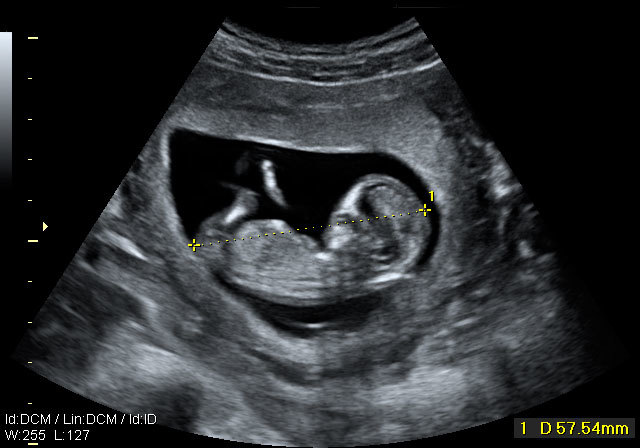

• semana 12

semana 12

El feto tiene la capacidad de respirar, orinar, tragar ,aprender y percibir el ruido.